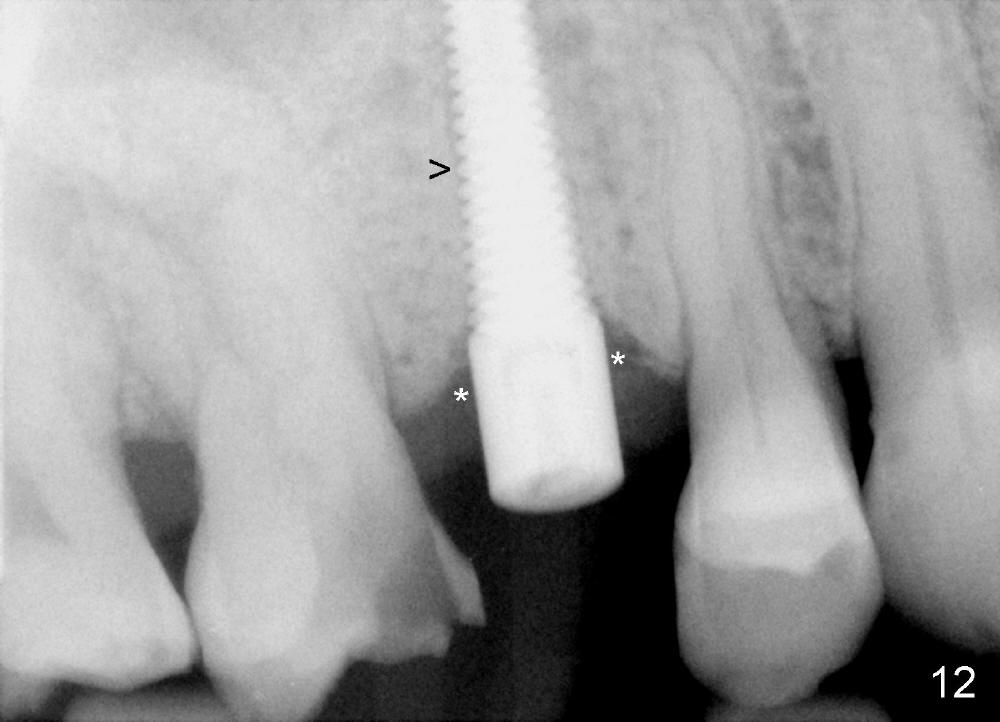

A 72-year-old man is a bruxer with #3 cusp fracture with chronic periapical radiolucency (Fig.1 *) and #4 acute crack. It appears reasonable to take care of emergency (#4 extraction and immediate implant (Fig.3-7: 4.5x20 mm, 45 Ncm)) followed by root canal therapy or extraction for #3. Eight (Fig.8) and 14 (Fig.9-11) days postop, the patient is doing fine and the wound heals normally. But he does not agree any treatment for #3, since it is asymptomatic in spite of a fistula associated with the tooth (Fig.8,9 >). Three months postop, the patient is still asymptomatic and is ready for #4 restoration since the tooth #28 cracks. Follow-up PA shows the persistent distal gap (Fig.12 >, as compared to Fig.4), accompanied with crestal bone resorption (*). Clinically the implant has mild mobility and light tenderness. The patient still refuses #3 treatment. It appears that the implant has failed to osteointegrate. In brief, do not place an immediate implant next to active infection.

Five and a half months postop, the distal gap appears to have reduced (Fig.13 >). Clinically the implant is stable and is ready for restoration. It is advisor able to watch those asymptomatic immediate implants with minimal mobility. It takes time to osteointegrate the immediate implant considering the peri-implant space.